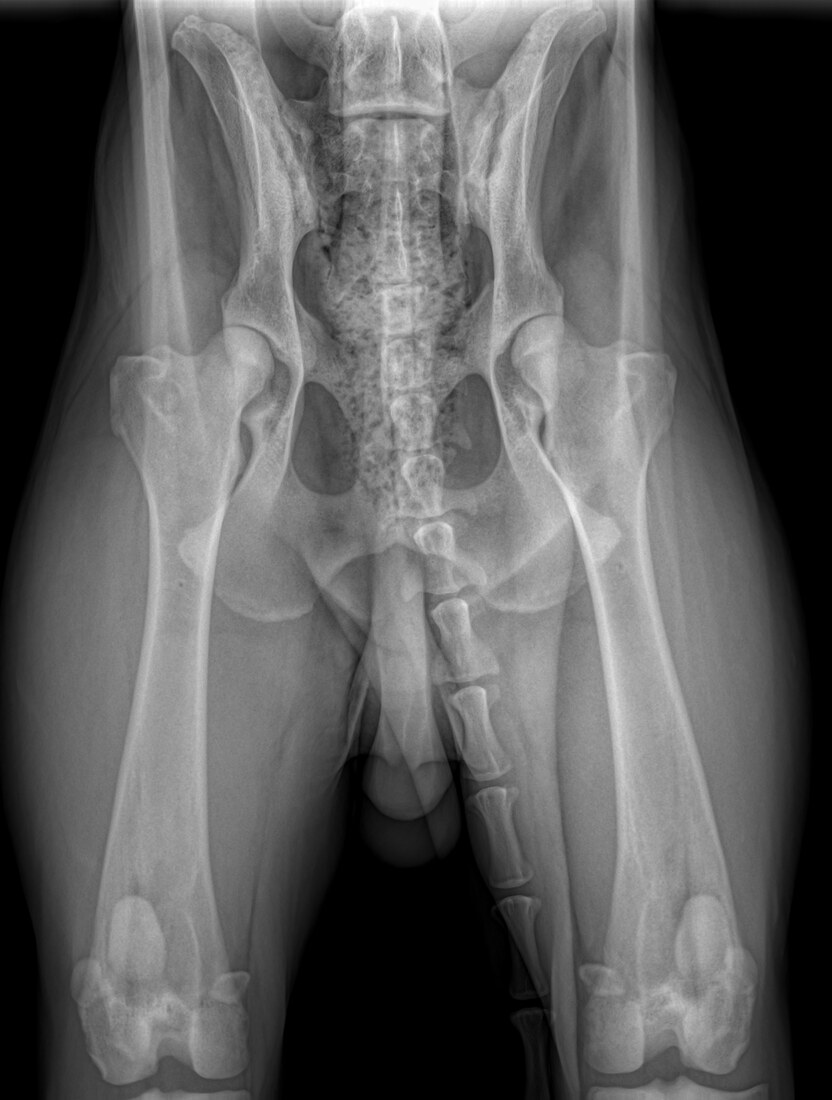

Bentley